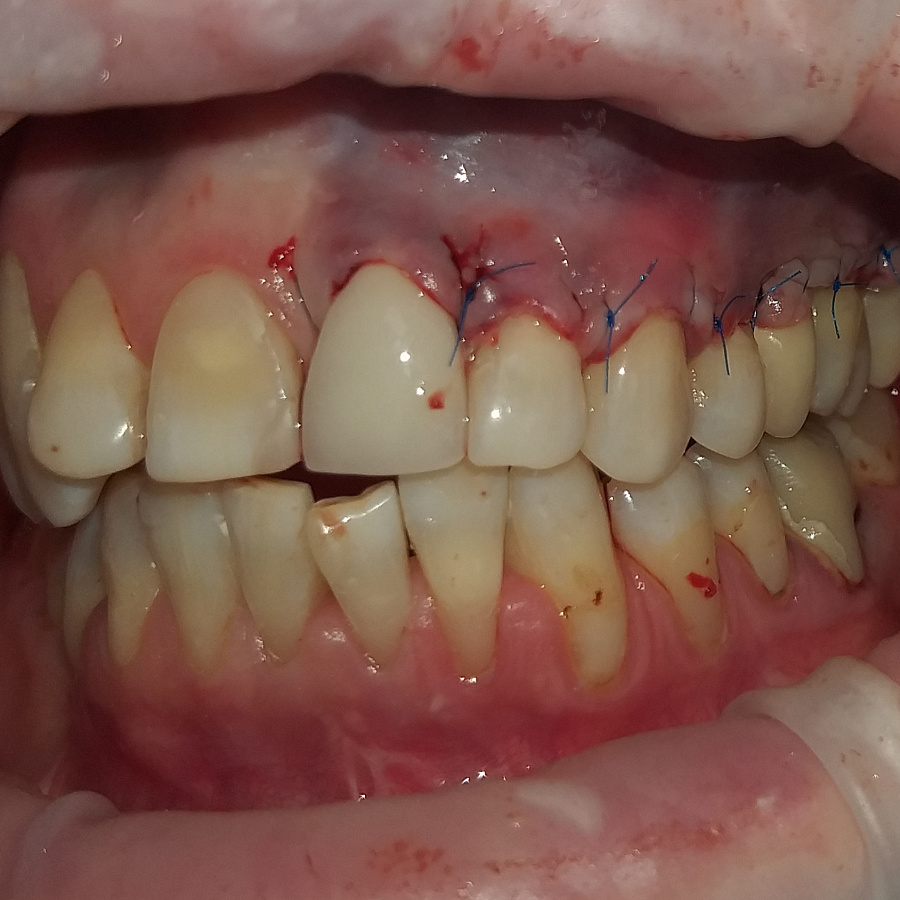

2. Операция по закрытию рецессии десны мягкими тканями - перемещение полнослойного слизистого лоскутка. Операцию проводил хирург Денис Черкашин.